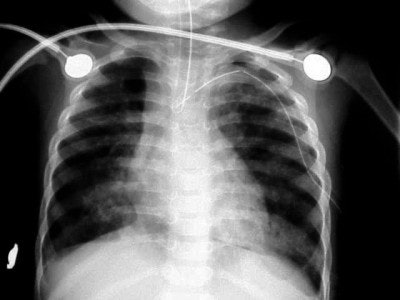

![]() |

| Figure 6 |

| Figure 7 |

| Figure 8 |

In figure 6 we have a 24-month-old who has been intubated, with a diagnosis of RSV. The film is slightly overpenetrated as we cannot clearly make out lung markings, but we can see the bronchial air shadow and the tip of the ETT (marker arrow), which is right at the carina (the bifurcation of the right and left mainstem bronchus). Doctors attempted to re-position the ETT and the left lung is ruptured causing a tension pneumothorax (arrow, figure 7).

In figure 8, the radiographic technique has been adjusted to show lung markings after the placement of a chest tube on the left. The chest tube, however, appears to be abutting the ETT, and notice the air shadow extending around the pericardium and along the diaphragm, consistent with the diagnoses of pneumomediastinum.